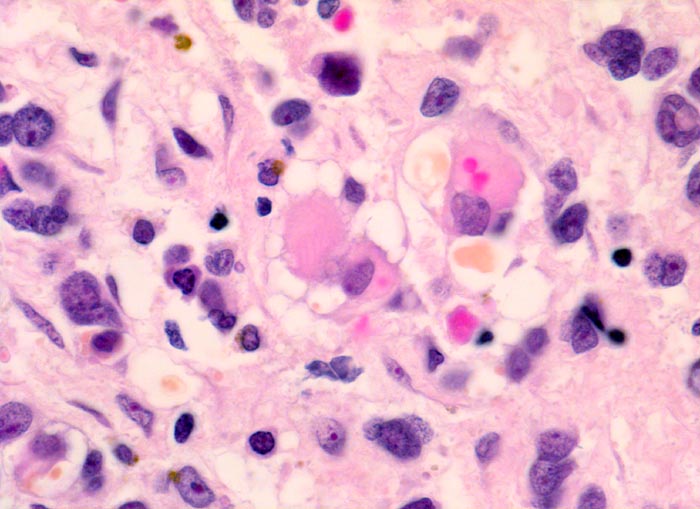

• Konjunktivalschleimhautfragment. Fibrinauflagerungen anstelle der langstreckig abgeschilferten konjunktivalen Zylinderepithelbedeckung (unten).

• Chronisches lymphoplasmazelluläres Entzündungsinfiltrat im subepithelialen Stroma mit unscharfer Begrenzung zu einem zellreichen soliden Tumor.

• Dieser besteht aus mesenchymalen Zellen mit unterschiedlicher Ausdifferenzierung.

• Die am wenigsten ausdifferenzierten Zellen zeigen wenig amphophiles Zytoplasma und ovale Kerne.

• Dominierend sind in diesem Tumor teils mehrkernige Rhabdomyoblasten mit reichlich eosinophilem Zytoplasma und exzentrischem Zellkern. Die Querstreifung des Zytoplasmas ist in der HE Färbung nur andeutungsweise erkennbar.

• "Spinnwebenzellen" mit peripheren Zytoplasmavakuolen.